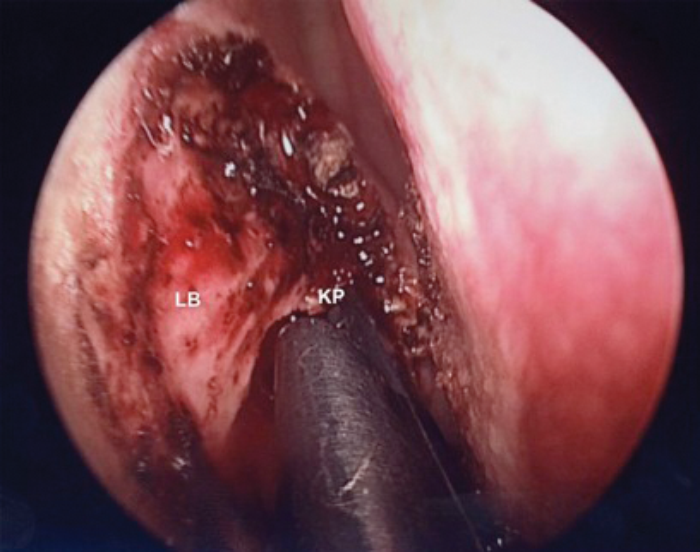

LB - Lacrimal bone KP - Kerrison Punch

Figure 2a. Removal of Lacrimal bone with Kerrison punch.